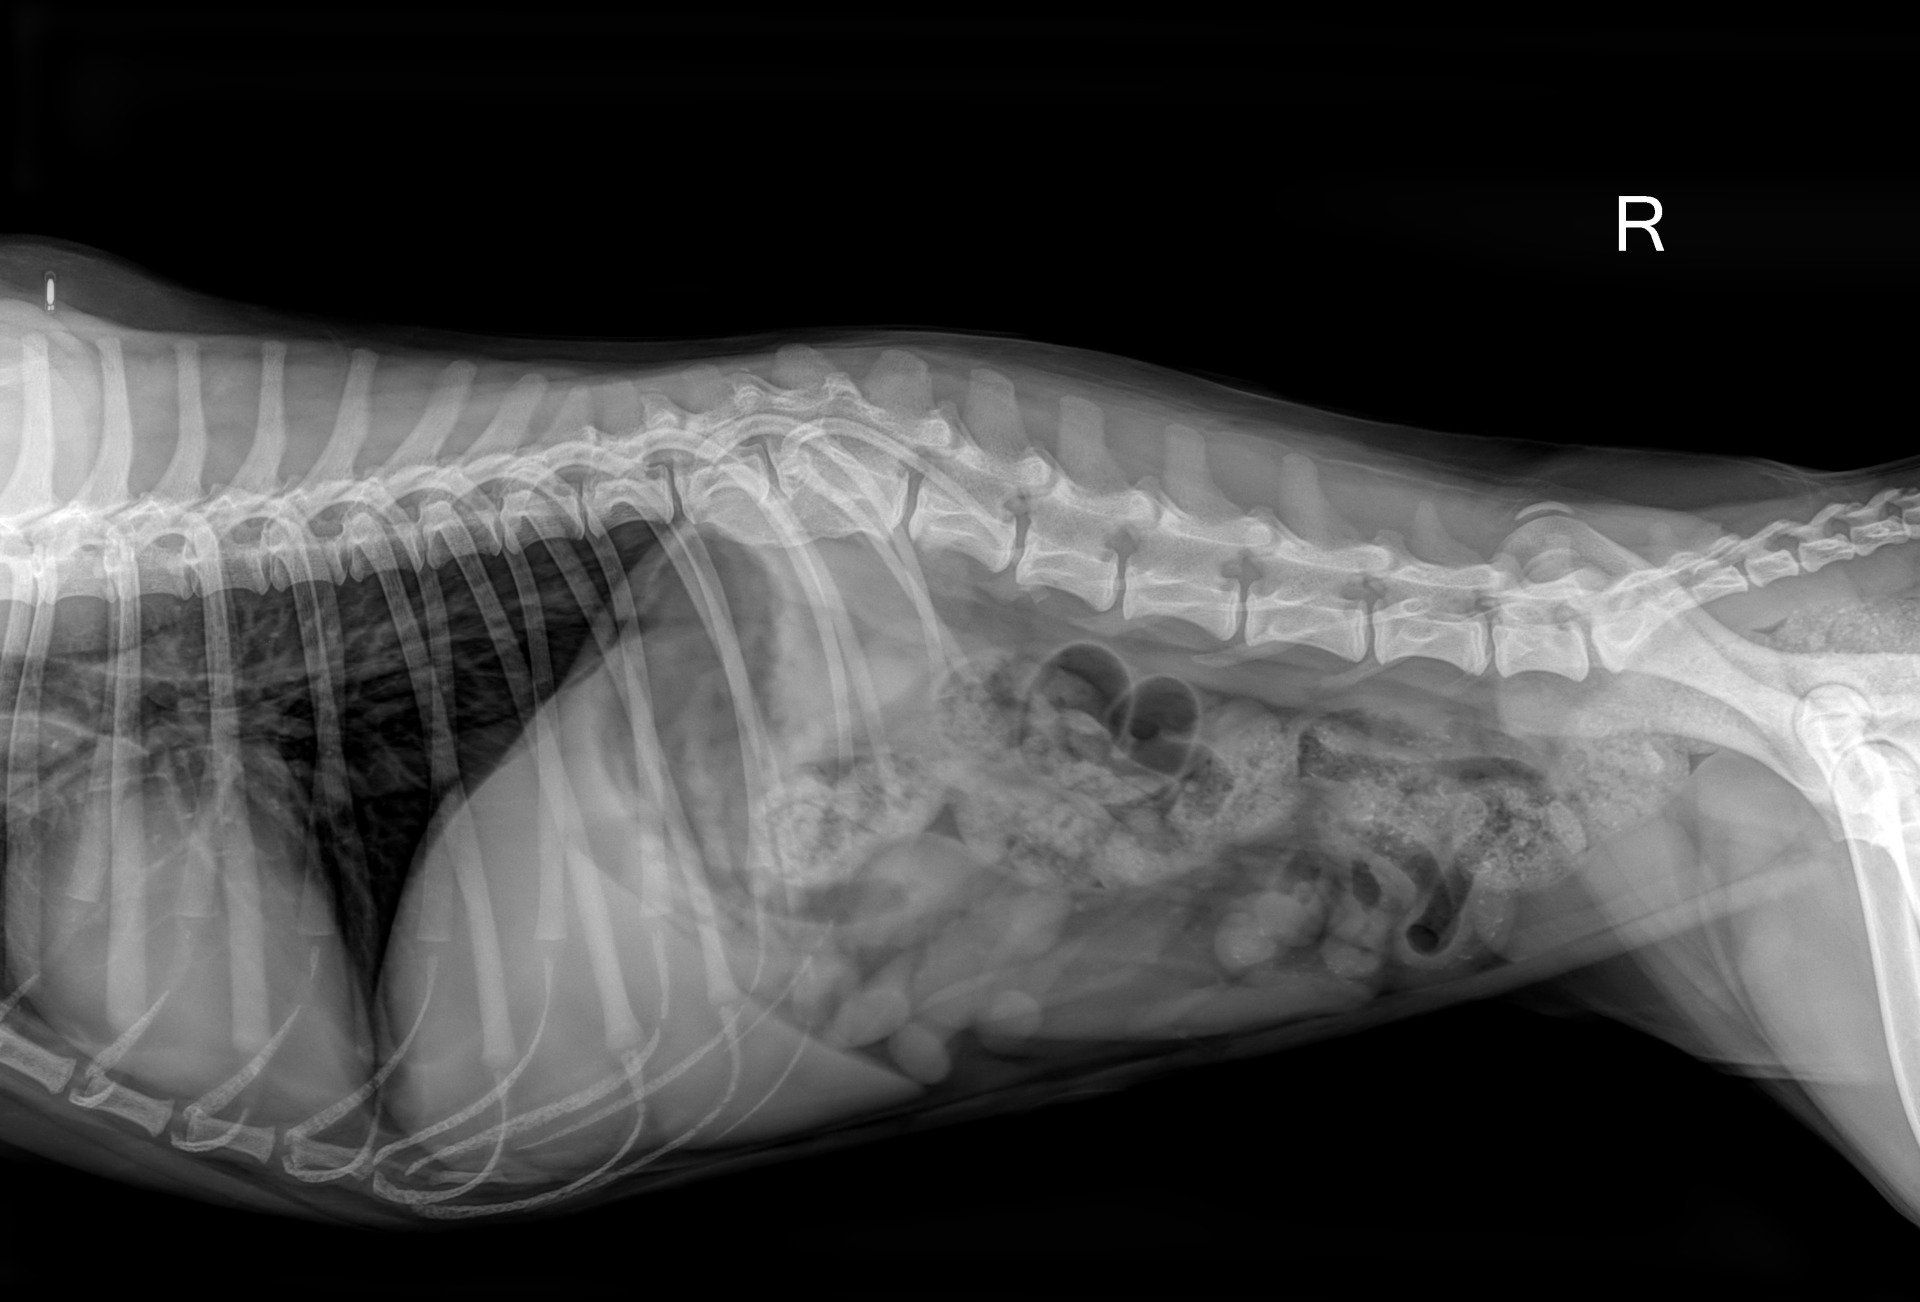

Dann hatten wir Baby ein gutes halbes Jahr bei uns in der Pflegestelle, haben sie medizinisch versorgen lassen und gefördert wo immer es ging. Wir haben sie bei einem Fachtierarzt in Bremen untersuchen und röntgen, sowie ihre Mittelohrentzündung behandeln lassen. An dem angebrochenen Rücken und der kaputten Kniescheibe konnte chirurgisch nichts mehr gerichtet werden, aber beide Stellen waren mittlerweile so stabil, das ein weiterer Schaden wahrscheinlich nicht zu erwarten war. Baby bekam nun viel Physiotherapie und ihr Zustand hat sich ständig verbessert. Zur Unterstützung ihres Knies wurde eine Bandage angefertigt, damit das Bein nicht ständig wegknickt.